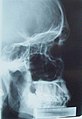

Röntgenbild eines männlichen Schädels